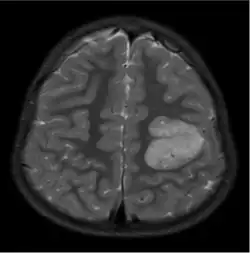

As características do GA são visíveis através de TC ou RM. Na RM, o GA aparece como lesões corticais bem delineadas, sólidas e hiperintensas em T2.[1] Outro traço diagnóstico é uma extensão para os ventrículos cerebrais adjacentes.[13]